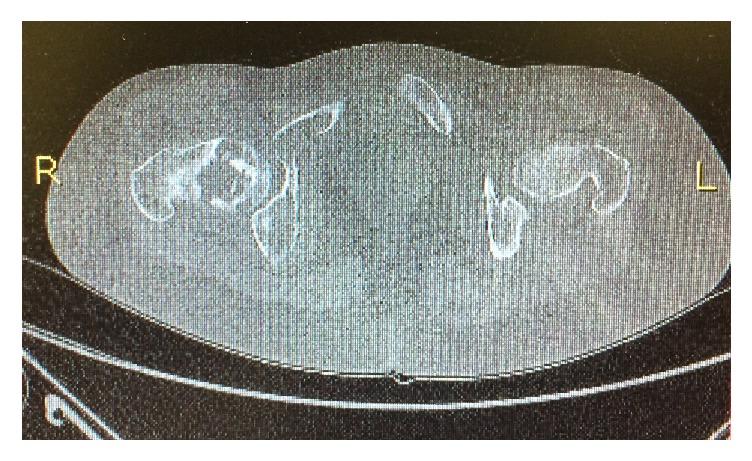

McCune-Albright syndrome (MAS) is a rare disease defined by the triad of polyostotic fibrous dysplasia of bone, café-au-lait skin spots, and precocious puberty. No available treatment is effective in changing the course of fibrous dysplasia of bone, but symptomatic patients require therapeutic support to reduce bone pain and prevent fractures and deformities. We report the case of a 27-year-old woman with MAS and severe fibrous dysplasia. She was diagnosed with MAS at 4 years of age and, during follow-up, she had multiple pathological fractures and bone pain refractory to treatment with bisphosphonates, tricyclic antidepressants, and opioids. The pain was incapacitating and the patient required a wheelchair. Intranasal calcitonin was then started, and, 30 days later, the patient already showed significant improvement in pain severity at the affected sites. After 3 months, she was able to walk without assistance. No adverse effects were observed, nor were any significant changes in serum levels of calcium, phosphorus, and alkaline phosphatase. Calcitonin has a well-recognized analgesic effect on bone tissue. Despite the small number of studies involving patients with MAS, calcitonin may be considered a short-term therapeutic option in cases of severe and refractory bone pain.